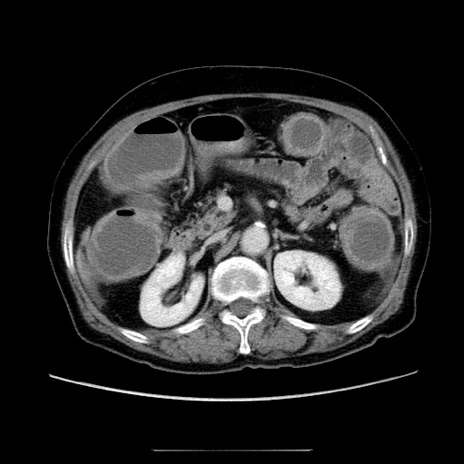

症例5(横断像)

【症例】70歳代女性

【主訴】お腹が張る

【現病歴】1週間くらい前から腹部膨満の自覚あり。昨日夜から増悪したため、本日救急外来受診。

【身体所見】意識清明、BT 36.5℃、BP 165/106mmHg、HR 80bpm、SpO2 98%、腹部:膨満、軟、自発痛・圧痛なし、触診にて不快感あり、腸蠕動音:減弱

【データ】WBC 12600、CRP 1.04